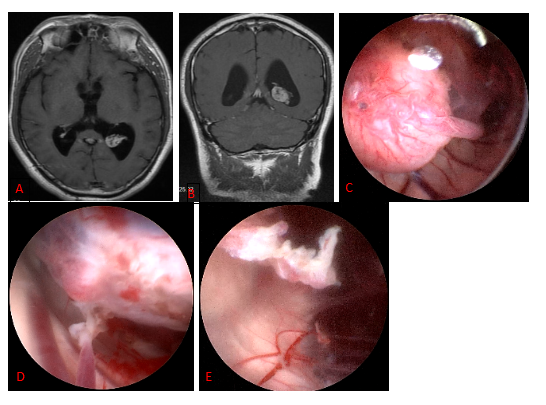

Figure 6. a pre-surgical MRI image; b illustration of scalp incision; c intraoperative screenshot, endoscopic view of 3 alternative fistula sites between the cyst and the basal pool: between the moto neurotic nerve and the cerebellar curtain margin; between the moto neurotic nerve and the internal carotid artery; and between the internal carotid artery and the optic nerve; d the basilar artery is visible below after fistula. a: cerebellar curtain b: internal carotid artery c: optic nerve d: moto neurotic nerve